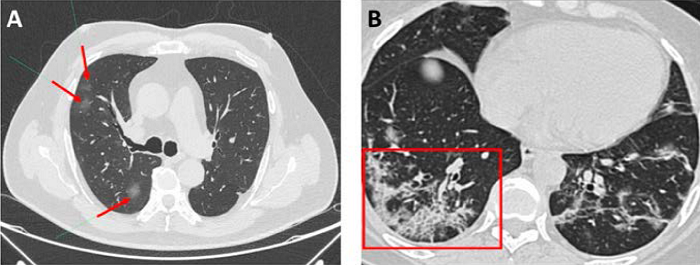

Los hallazgos tomográficos de la COVID-19 son variados y han sido descritos por múltiples series.44,45,46 Aunque dichos hallazgos dependen de la severidad y del estadio de la enfermedad,47 la evidencia sugiere que la principal característica es la presencia de opacidades en vidrio esmerilado (Figura 4A).42 La mayoría de los pacientes presentan un compromiso bilateral, que involucra múltiples lóbulos pulmonares con un marcado predominio de los segmentos inferiores. Otra de las características típicas es que las lesiones siguen una distribución subpleural o periférica.42,43,47 Se ha reportado que las opacidades en vidrio esmerilado pueden asociarse con reticulaciones intralobulares (producto del engrosamiento de los septos intralobulillares), produciendo el patrón en empedrado (crazy paving) (Figura 4B) de 35 a 40 %4 de los casos.44,45 Además, dichas opacidades en vidrio esmerilado pueden confluir y estar acompañadas de áreas de consolidación, produciendo el denominado signo del halo en 64 % de los pacientes.44

Siguiendo el esquema de monitoreo propuesto, es posible tener una visión oportuna de los cambios que se presentan en el seguimiento de los pacientes. Hemos reportado cómo se ve la modificación de las pruebas de función respiratoria durante los primeros seis meses de seguimiento en una paciente con neumonía grave por COVID-19.57 Claramente se puede apreciar cómo los valores van aumentando a medida que pasan los meses luego de haber iniciado tratamiento con rehabilitación pulmonar y oxigenoterapia durante las primeras semanas de convalecencia (Cuadro 5). Del mismo modo, al inicio de la enfermedad se observan imágenes de consolidación asociada a un patrón en empedrado en la TACAR (Figura 6A); en tanto que a los seis meses, en la TACAR de control es posible observar bronquiectasias de tracción, engrosamiento de septos interlobulillares y tenues infiltrados en vidrio esmerilado ( Figura 6B).